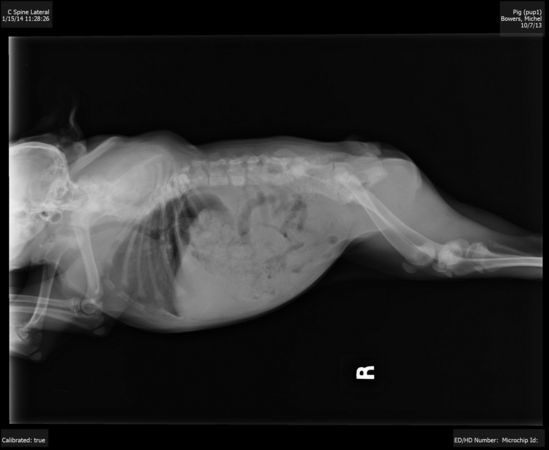

У Хрюши неполный набор спинных позвонков, одна часть позвонков отсутствует, другие из них срослись, а третьи были перекручены вместе со спинным мозгом

Также у Хрюши отсутствует пара ребер и суставы её бедер вывернуты в неправильной форме

У неё большие проблемы с тем участком спинного мозга, который находится ближе к шее